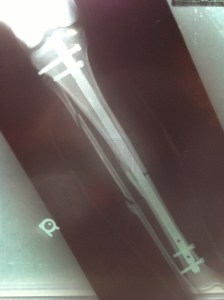

This is my running history, I started running in California when I was young and continued on in to high school. It is there where I learned and loved to compete. With my fastest time in the 1500 being 4:47 I was looked at by many universities. But unfortunatley at this time I was starting to feel burnt out from running and started seeing my times increase. So to avoid the pressure of any big university I chose to run for a junior college instead. After about a year of attending the junior college I decided to move to Utah to continue my education. I continued to run but not competitivley. I continued to feel sluggish as I did that senior year of high school. Then on Christmas day of 2001 driving home from work from the local ski resort I was in an accident. Heading down the canyon I drove over black ice that spun my Honda Civic out of control into the middle mediam. The impact force then caused my car to slide across the road on to the shoulder hitting the gaurd rail. Although, the momentum was great enough to rip the rail out if its anchors and it folded on its self. This caused a strengthing effect and the doubled up metal pushed through the front passenger side and out through the drivers door. The guard rail tore through the door of the Civic and out the otherside taking the seats with it. Miraculously leaving only one piece of precious cargo, ….me. Once the enertia ceased I was left sitting on top of the doubled up guard rail pinned against the steering wheel, legs caught between the clutch and the brake. It was truly a miracle I survived. The damage, although for me a runner was very serious, was very minimal and superficial. The trauma included the tearing of all ligaments in the left knee, two broken legs with one major compound fracture.

As one could imagine, this put my running on hold. I was hospitalized for two weeks followed by four months of being wheelchair bound not to mention the massive rod hammered into my right leg.